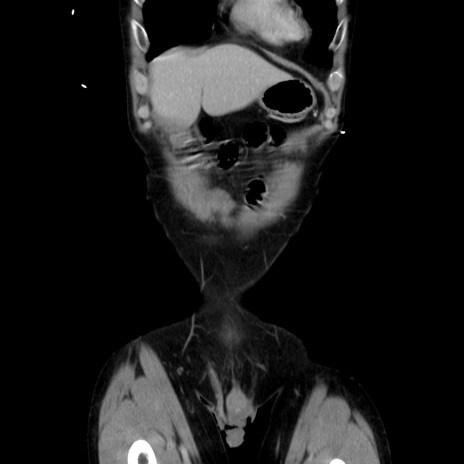

症例37(冠状断像)

【症例】40歳代 男性

【主訴】腹痛

【現病歴】4時間ほど前に電車に乗車中に臍部上より腹痛出現。徐々に増悪し起立困難となり、救急外来受診。生ものは数日食べていない。今朝お雑煮を食べた。

【身体所見】BT 36.8℃、BP 117/84mmHg、HR 91/min、SpO2 97%、苦悶様、腹部:臍上部広範囲圧痛あり、反跳痛±

【データ】WBC 8100、CRP 0.03